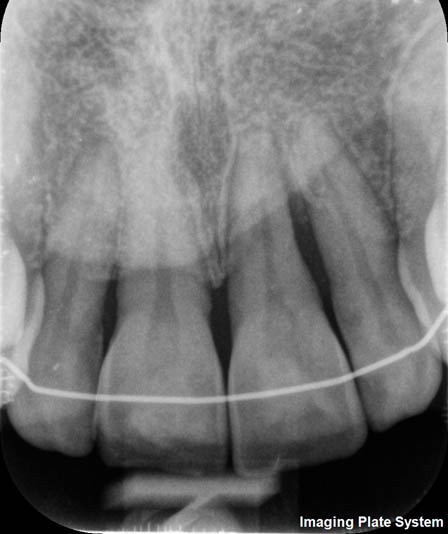

The rehabilitation of this periodontally compromised tooth required a multidisciplinary approach, combining both periodontal and orthodontic treatments.

Following an initial phase of non-surgical periodontal therapy aimed at removing subgingival calculus, Dr. Anna Mariniello performed both upper and lower alignment using a lingual, non-bracket orthodontic technique, employing active retainers applied to the lingual surfaces of the teeth.